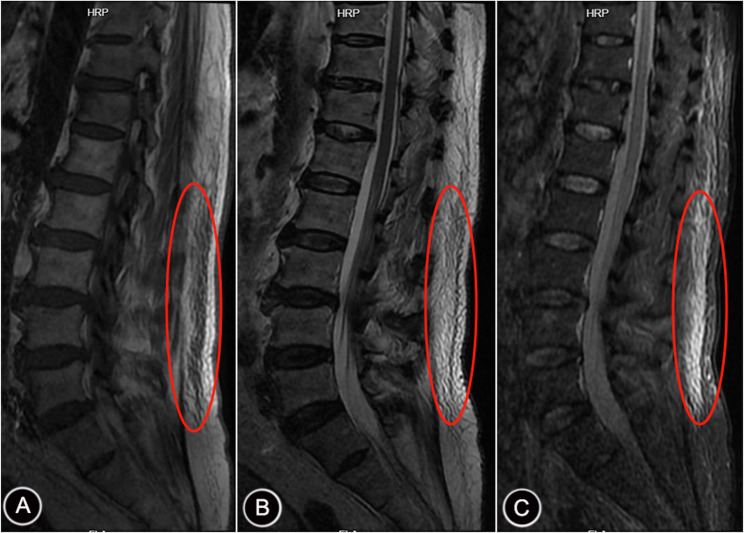

Methods: The clinical data of 351 patients with PD from October 2019 to September 2022 were retrospectively analyzed. MRI images were used to evaluate the presence or absence of TLFI. Binary logistic regression analysis was used to determine the independent risk factors for TLFI in patients with PD. The independent predictors were used as predictors to construct a nomogram model, and the predictive efficacy of the model was evaluated by receiver operating characteristic (ROC) curves and calibration curves (CCs). Decision curve analysis (DCA) was used to evaluate the clinical application value of the model.